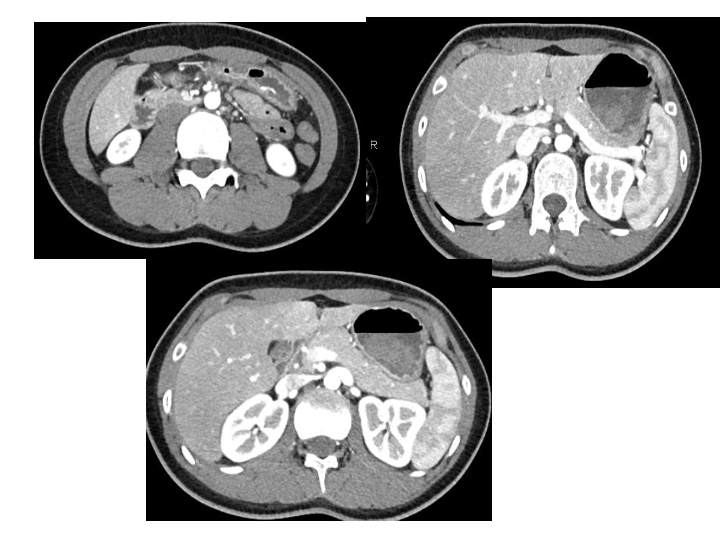

腹部创伤的救治案例